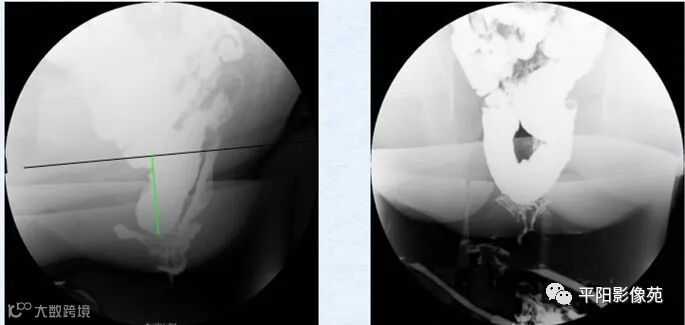

会阴下降(perineum descending,PD)是指用力排便时肛上距≥31mm(经产妇≥36mm)者。伴有其他异常时称之为会阴下降综合征(descending perineum syndrome,DPS)。(图1)

图1 力排时肛上距明显增大>31mm